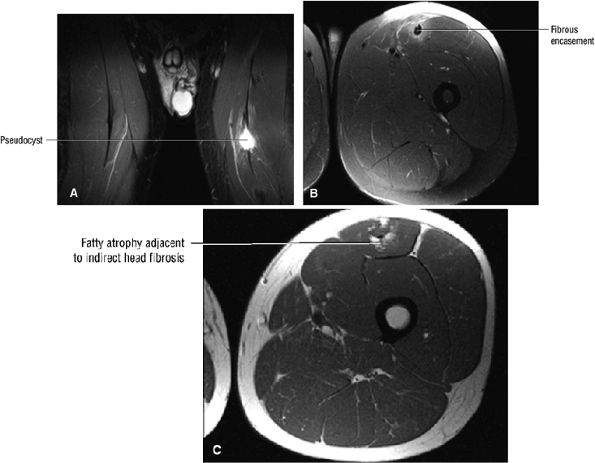

FIGURE 3.6 ● RECTUS FEMORIS The rectus femoris flexes the thigh (hip) and extends the leg (knee). Of the four quadriceps muscles (the vastus lateralis, vastus medialis, vastus intermedius, and rectus femoris), only the rectus femoris has an origin that crosses the hip joint. Soccer, football, and basketball players and track and field athletes are at risk for distal musculotendinous junction injuries and proximal intrasubstance tears of the musculotendinous junction of the indirect head of the rectus.

|

![]() |